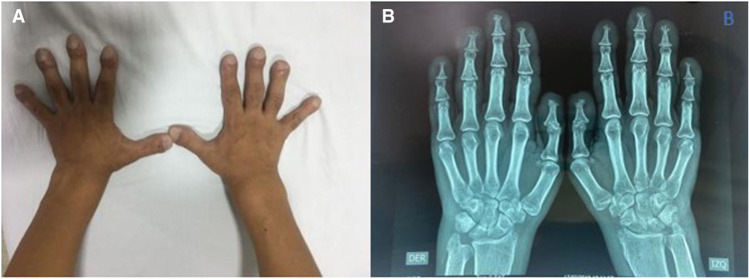

Here, we highlight the case of a 31-yr-old man who had clinical features of primary hypertrophic osteoarthropathy (PHOAR) and harbored a homozygous variant (c.38C > A, p.Ala13Glu) in the HPGD gene, as indicated by whole-exome sequencing (WES). This variant has been previously classified by our laboratory as a variant of uncertain significance (VUS). However, another patient with the same phenotype and the same homozygous variant in HPGD was subsequently reported. In reassessing the variant, the absence of this variant in the gnomAD population database, supporting computational predictions, observation in homozygosity in two probands, and specificity of the phenotype for HPGD, all provide sufficient evidence to reclassify the HPGD c.38C > A, p.Ala13Glu variant as likely pathogenic.